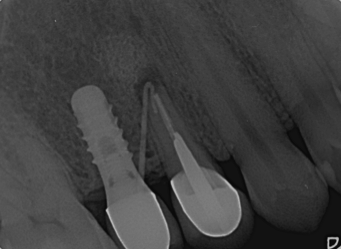

根尖切除術

治療前